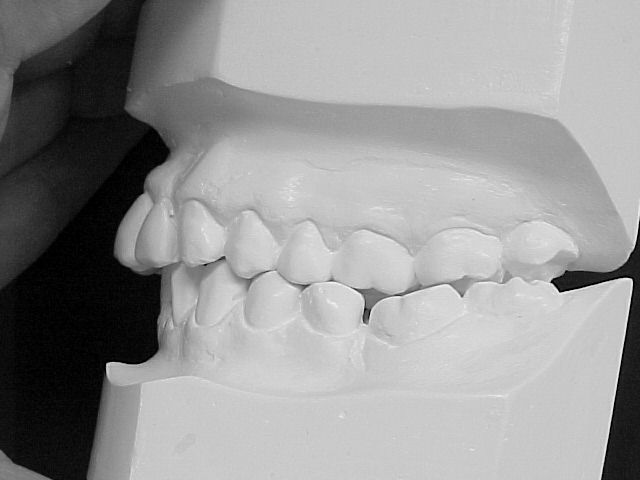

Modelos de estudo antes do tratamento

|

Modelos em gesso após o tratamento